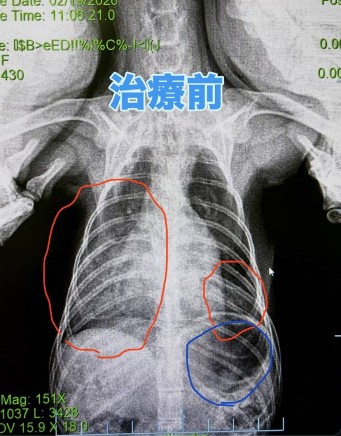

レントゲンを撮ったところ肺水腫(赤丸)が認められました。

また苦しいために必死で息をしてるため胃に空気も溜まっています(青丸)